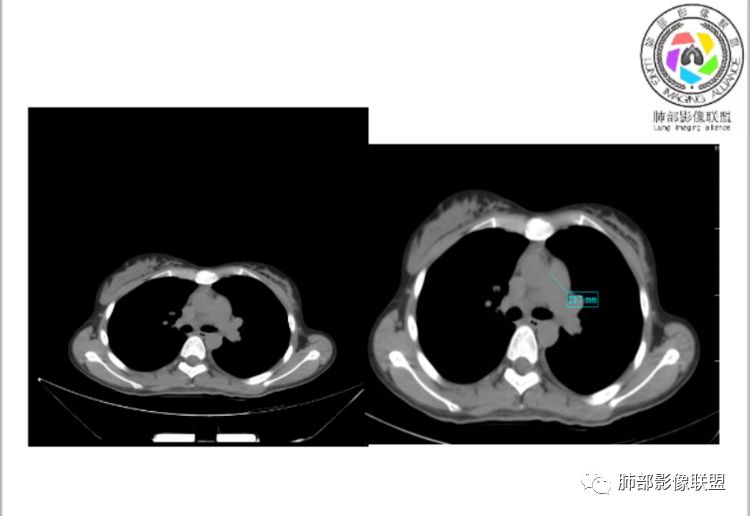

笨丫头:肺栓塞也会发热呀王江涛:肺内子宫内膜异位症,合并梗死出血Lenle董:外围渗出性改变,出血?左下肺的支气管镜不会看张帅:呼吸困难比较难判断,尤其对于一个有胸痛的患者来说@唐大川新沂市人民医院呼吸科风之子:对,要警惕子宫内膜异位症岁月:病史:女,19岁;右侧胸痛2天;血常规17.4,中性粒75.7%,右下肺斑片影;月经不调,雌激素?治疗;D2高,3974.78,支气管镜阴性。治疗方式,抗炎。病史诊断方向:肺栓塞?影像:首先找肺栓塞影像。6天后CT可疑肺栓塞;作者量肺动脉23.7mm,提示什么?好像和同层面主动脉宽度相当,先心病?肺血无明显改变?双肺斑片影,左侧磨玻璃,边界清楚,还有些散在不清楚,左侧为甚,胸膜下贴,三角形?左侧少了胸水;诊断:肺栓塞;鉴别:先心合并肺栓塞?肺炎。

张帅:好多老师都在说肺动脉增宽。肺动脉增宽标准是多少?程磊:29。或者比同层主动脉比值大于等于1

张帅:我量的虽然不标准,但不到24

CTPA(CT断层肺血管造影)是对疑似PE患者肺血管系统成像的首选方法,可直观判断肺栓塞的程度和形态,以及累及部位及范围,可以从直接或间接征象进行诊断,但是对亚段及远段肺动脉血栓敏感性较差,联合肺动脉造影可以使PE诊断敏感性增强。

CTPA直接征象:

1、肺动脉中央部分充盈缺损

2、偏心性或附壁充盈缺损

3、骑跨型血栓

4、完全型充盈缺损,动脉截断,远端动脉分支内无造影剂

CT平扫及间接征象:

1、一个或多个胸膜下斑片高密度影(梗死、出血、肺不张、肺水肿、炎性渗出),典型为胸膜下楔形影 ,尖端指向肺门

2、肺动脉高压(中心肺动脉扩张),有时可见肺动脉区高密度影。